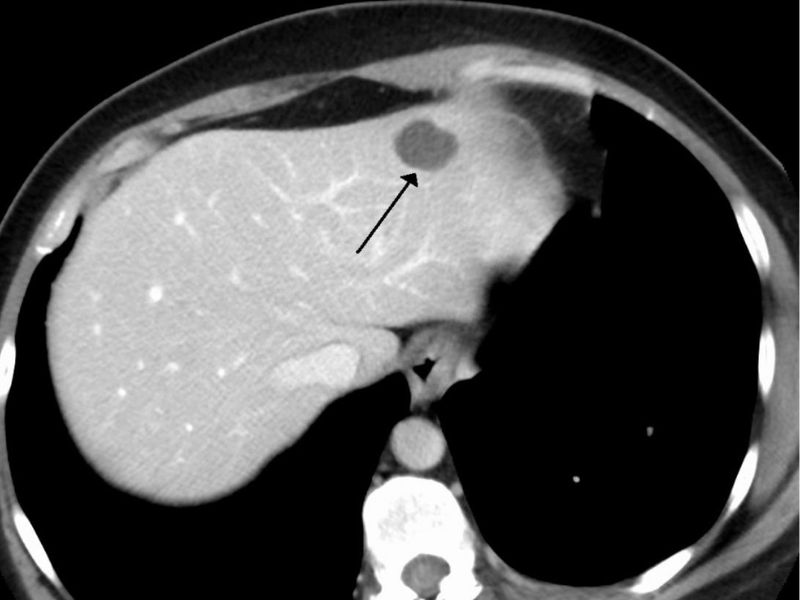

U máu gan là loại u máu phổ biến nhất trong nhóm u máu nội tạng. Thông thường, u máu trong gan ít khi gây ra triệu chứng. Tuy nhiên, nếu u máu gan phát triển lớn hơn 4 cm, bệnh nhân có thể gặp phải các triệu chứng như đau tức hoặc cảm giác đầy bụng.

Tỷ lệ mắc u máu gan ở người trưởng thành dao động từ 5% đến 7%, và nữ giới có khả năng mắc bệnh cao hơn nam giới. Các yếu tố như việc sử dụng thuốc tránh thai hoặc thay đổi nội tiết tố trong thai kỳ có thể liên quan đến sự hình thành u máu gan.

U máu gan thường lành tính và việc phát hiện u máu gan thường được thực hiện qua các phương pháp cận lâm sàng như siêu âm hoặc chụp cắt lớp vi tính. Vì gan không có dây thần kinh cảm giác nên hầu hết người bệnh rất khó nhận biết u máu gan cho đến khi phát hiện qua các xét nghiệm.

Các kỹ thuật chẩn đoán hình ảnh như siêu âm, chụp X-quang, CT hay chụp cộng hưởng từ MRI đóng vai trò quan trọng trong việc xác định chính xác u máu và giúp bác sĩ phân biệt u máu với các tình trạng khác như dị dạng mạch máu não, u nang bạch huyết, hạch bạch huyết hoặc các khối u ác tính như angiosarcoma (u mạch máu ác tính). Bên cạnh đó, phương pháp chụp hình mạch máu có sử dụng thuốc cản quang cũng có thể được sử dụng.